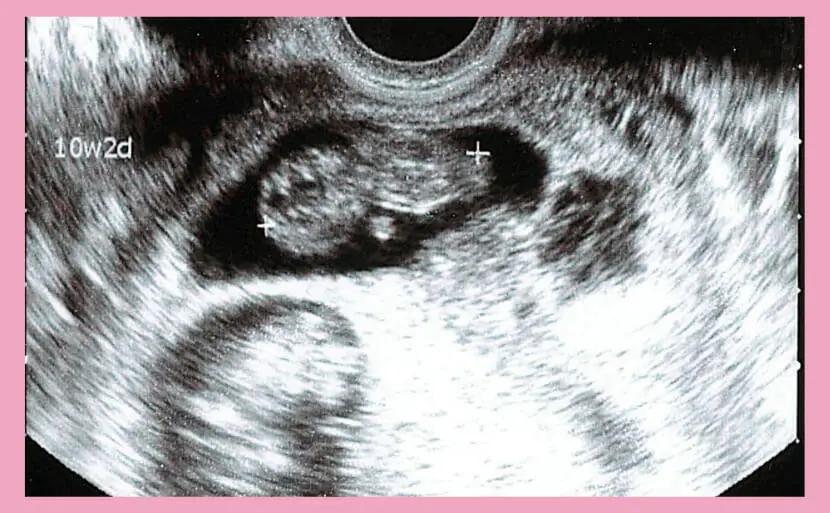

心拍や動きの確認

妊娠10週になると、超音波検査で赤ちゃんの心拍を安定して確認できるようになります。 心拍数は毎分120〜160回程度が一般的で、成長状態を知る重要な指標です。 まだ母親が胎動を感じることはありませんが、エコーでは手足を動かす様子が見える場合もあります。 こうした動きは、神経や筋肉が順調に発達している証拠です。 心拍や動きを確認することで、赤ちゃんが元気に育っている実感を得られるでしょう。

妊娠10週の胎児は頭殿長約3〜4センチ、体重約4グラムが目安で、手足の形が整い、超音波で心拍や小さな動きも確認しやすくなります。